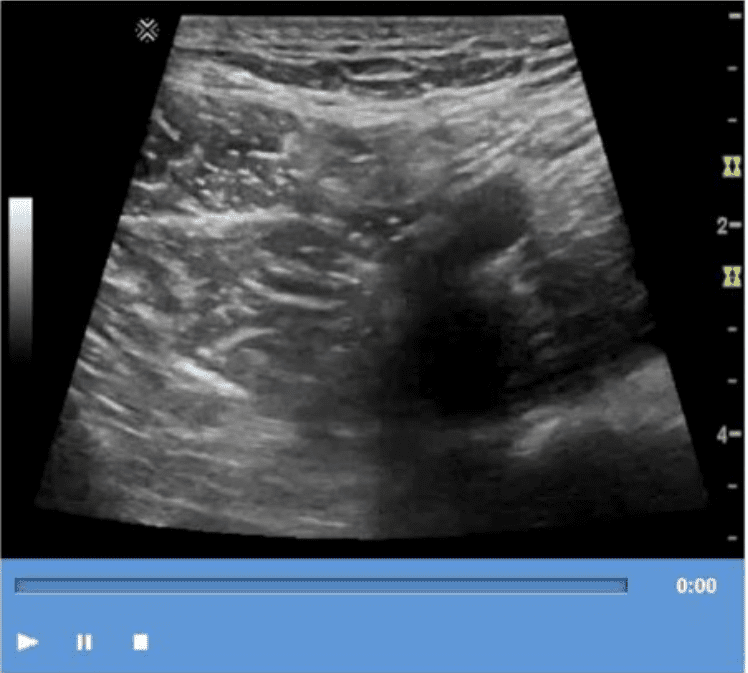

Which technique is used to demonstrate the finding in this video?